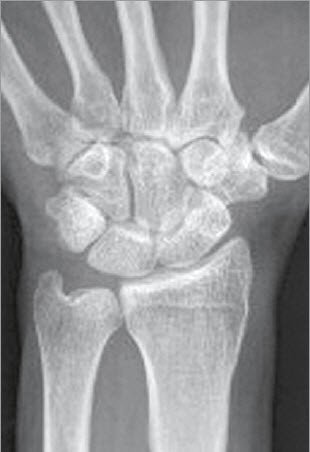

Eine Verdachtsdiagnose kann bereits durch die Patientenbefragung und das aktuelle Beschwerdebild gestellt werden. Gesichert wird die Diagnose einer Arthrose dann durch ein Röntgenbild. Findet sich nur eine leichte Arthrose, müssen möglicherweise Zusatzuntersuchungen durchgeführt werden. Bei fortgeschrittenen Arthrosen mit Gelenkzerstörung findet sich im Röntgenbild nur noch ein schmaler oder auch gänzlich fehlender Gelenkspalt (Abb. 1a bis 1c).